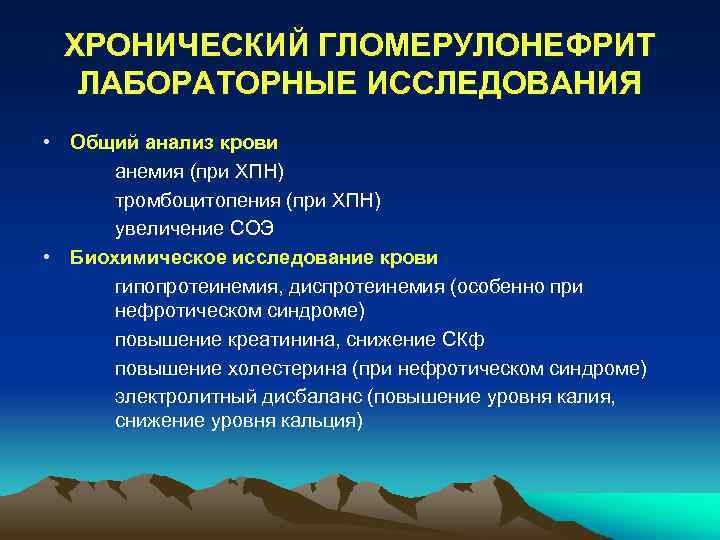

Механизм остро го диффузного гломерулонефрита